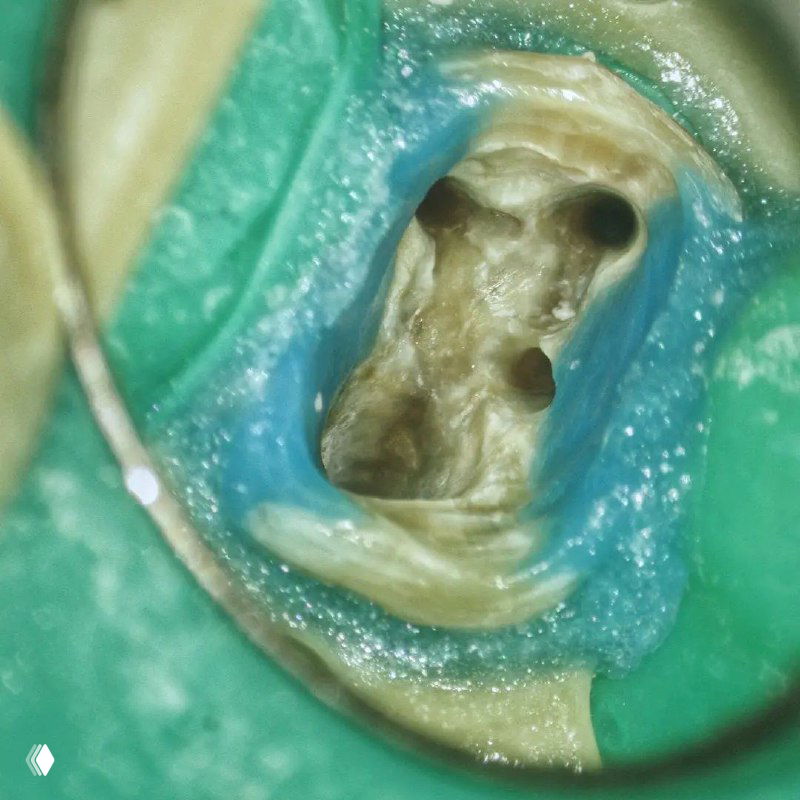

5 оттенков MB2 или долой предрассудки

- классическое расположение устья в 2 мм от МВ1 канала

- МВ2 отходит из МВ1

- устье МВ2 расположено посредине между МВ1 и небным каналами

- устье МВ2 расположено рядом с небным каналом

- внезапный МВ3 😎